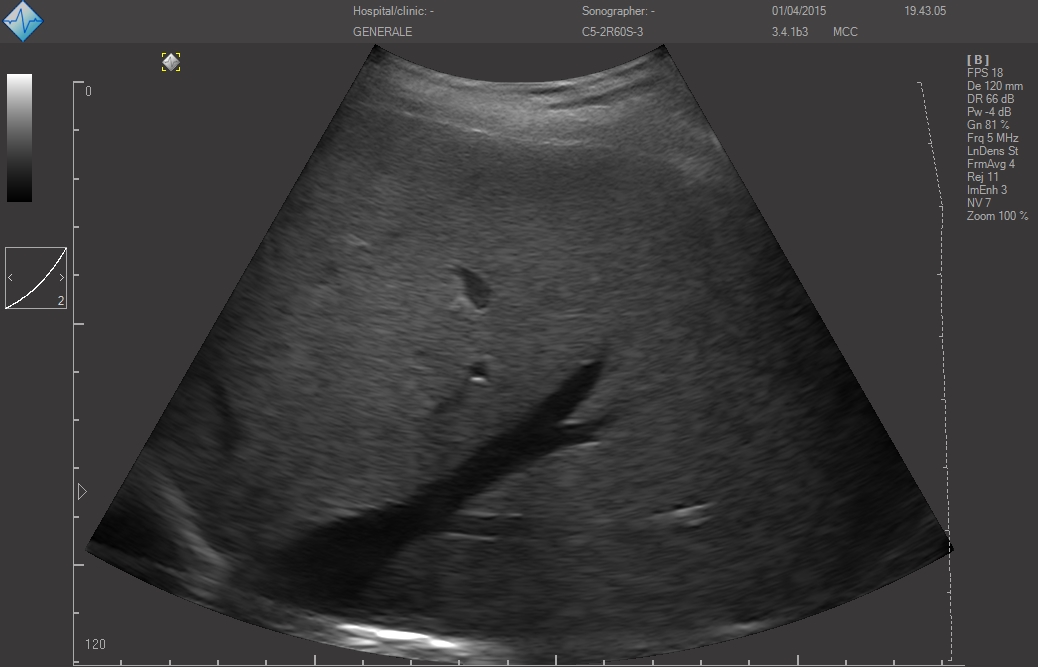

Исследование FAST (Сфокусированная сонографическая оценка при травме) позволяет выявить наличие жидкости в предполагаемых клинических условиях, визуализируя 10 структур или пространств в четырех областях:

- Тазовой

Хотя неотложный ультразвуковой протокол E-FAST был разработан для ускорения оказания помощи пострадавшим пациентам, применение его компонентов оказалось эффективным в случае использования портативного аппарата УЗИ (point-of-care ultrasound - POCUS) для обследования неповрежденных пациентов с гипотензией с целью выявления свободной жидкости, образовавшейся по другим причинам (например, при разрыве при внематочной беременности, аневризме брюшной аорты).